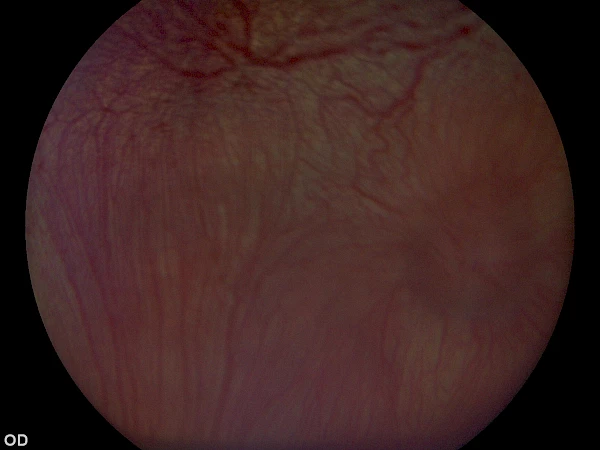

Vitreoretinale Chirurgie (Netzhautoperation, Anlegen der Netzhaut eines Hundes), v. Chris Dixon Vitreoretinale Chirurgie (Netzhautoperation, Anlegen der Netzhaut eines Hundes), v. Chris Dixon